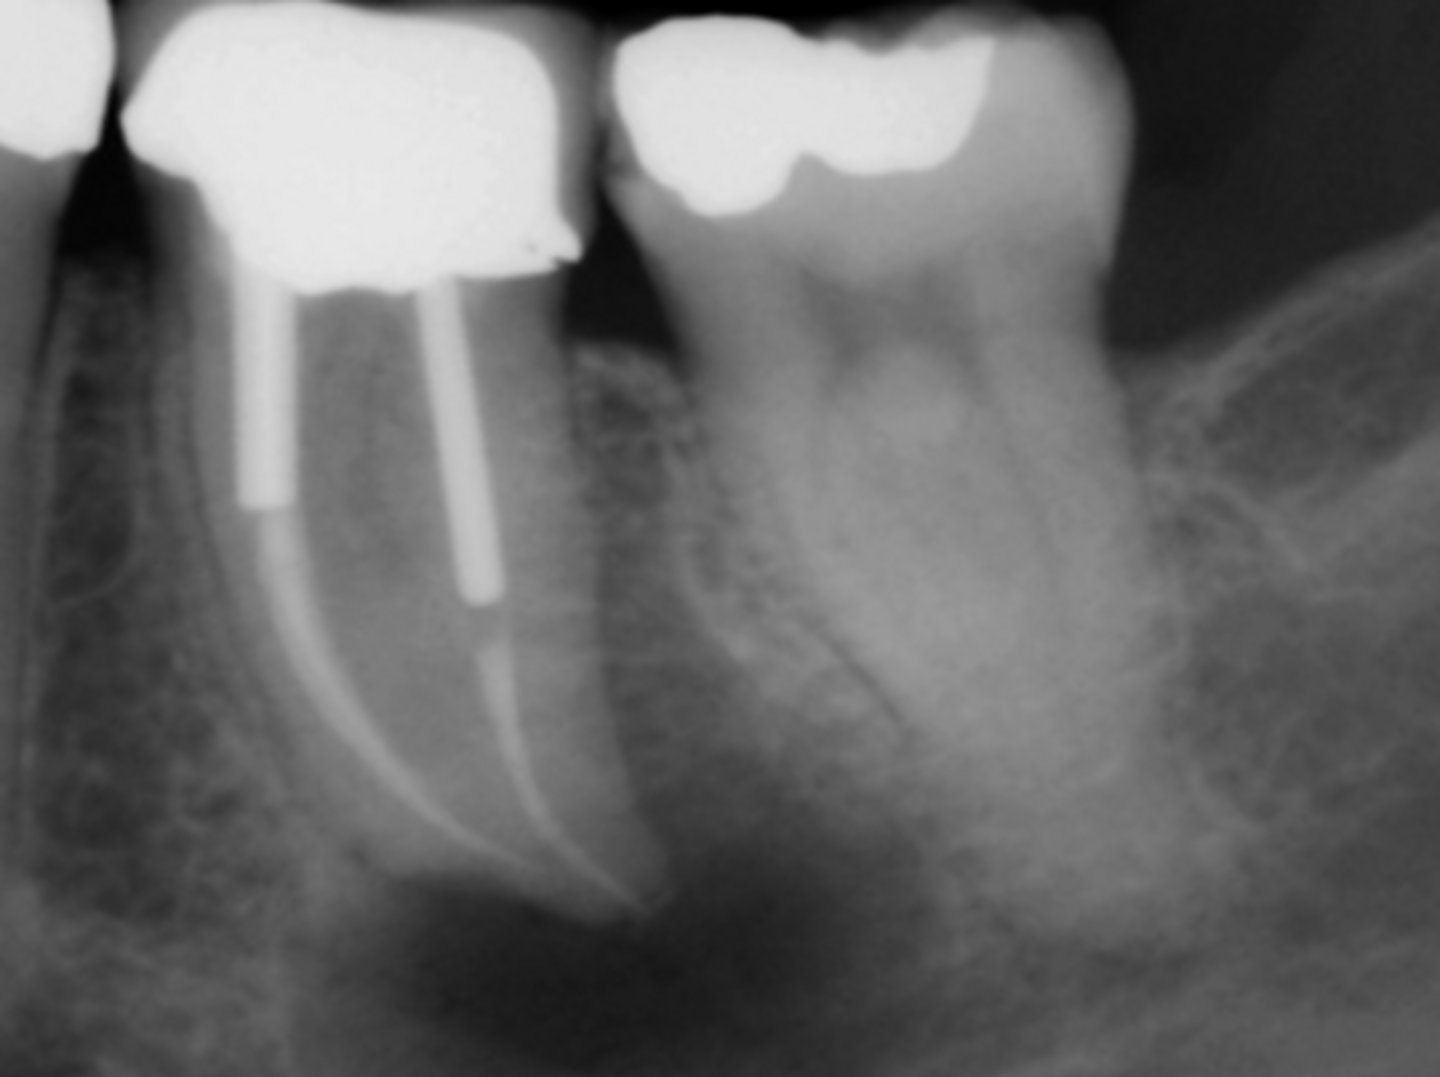

Infected silver point (Retreatment should be attempted first)

What is the cause of this apical radiolucency?